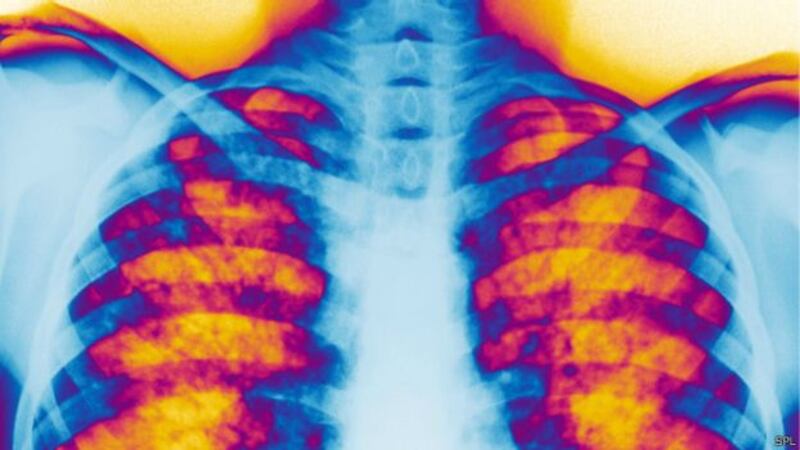

إنّ سبب هذا المرض هو وجود طفرة في الجين المسؤول عن عمليه تنظيم تبادل الأملاح والسوائل على مستوى الخلايا(CFTR). وبسبب هذا الخلل الفسيولوجي ينتج عنه سائل مخاطي لزجا جدا بحيث يشبه قوامه الغراء. يتراكم هذا السائل المخاطي اللزج في جميع أنحاء الجسم مما يسبب انسداد في الأنابيب والقنوات والممرات خاصة في الرئتين والبنكرياس.

وذكرت الدكتورة سمية بنت جمعة العريمية طبيبة استشارية أولى الجهاز التنفسي والحساسية في الأطفال ورئيسة وحدة الجهاز التنفسي للأطفال في المستشفى السلطاني : يتم تشخيص المرض في سن مبكرة جدا بسبب ظهور الأعراض غالبا خلال فترة الطفولة ، إن هذا المرض يؤثر بشكل رئيسي على الجهاز التنفسي والجهاز الهضمي، بحيث يعاني المريض من التهابات تنفسيه متكرره ومشاكل في التغذية والهضم بالإضافة إلى مشاكل في النمو والضعف العام.